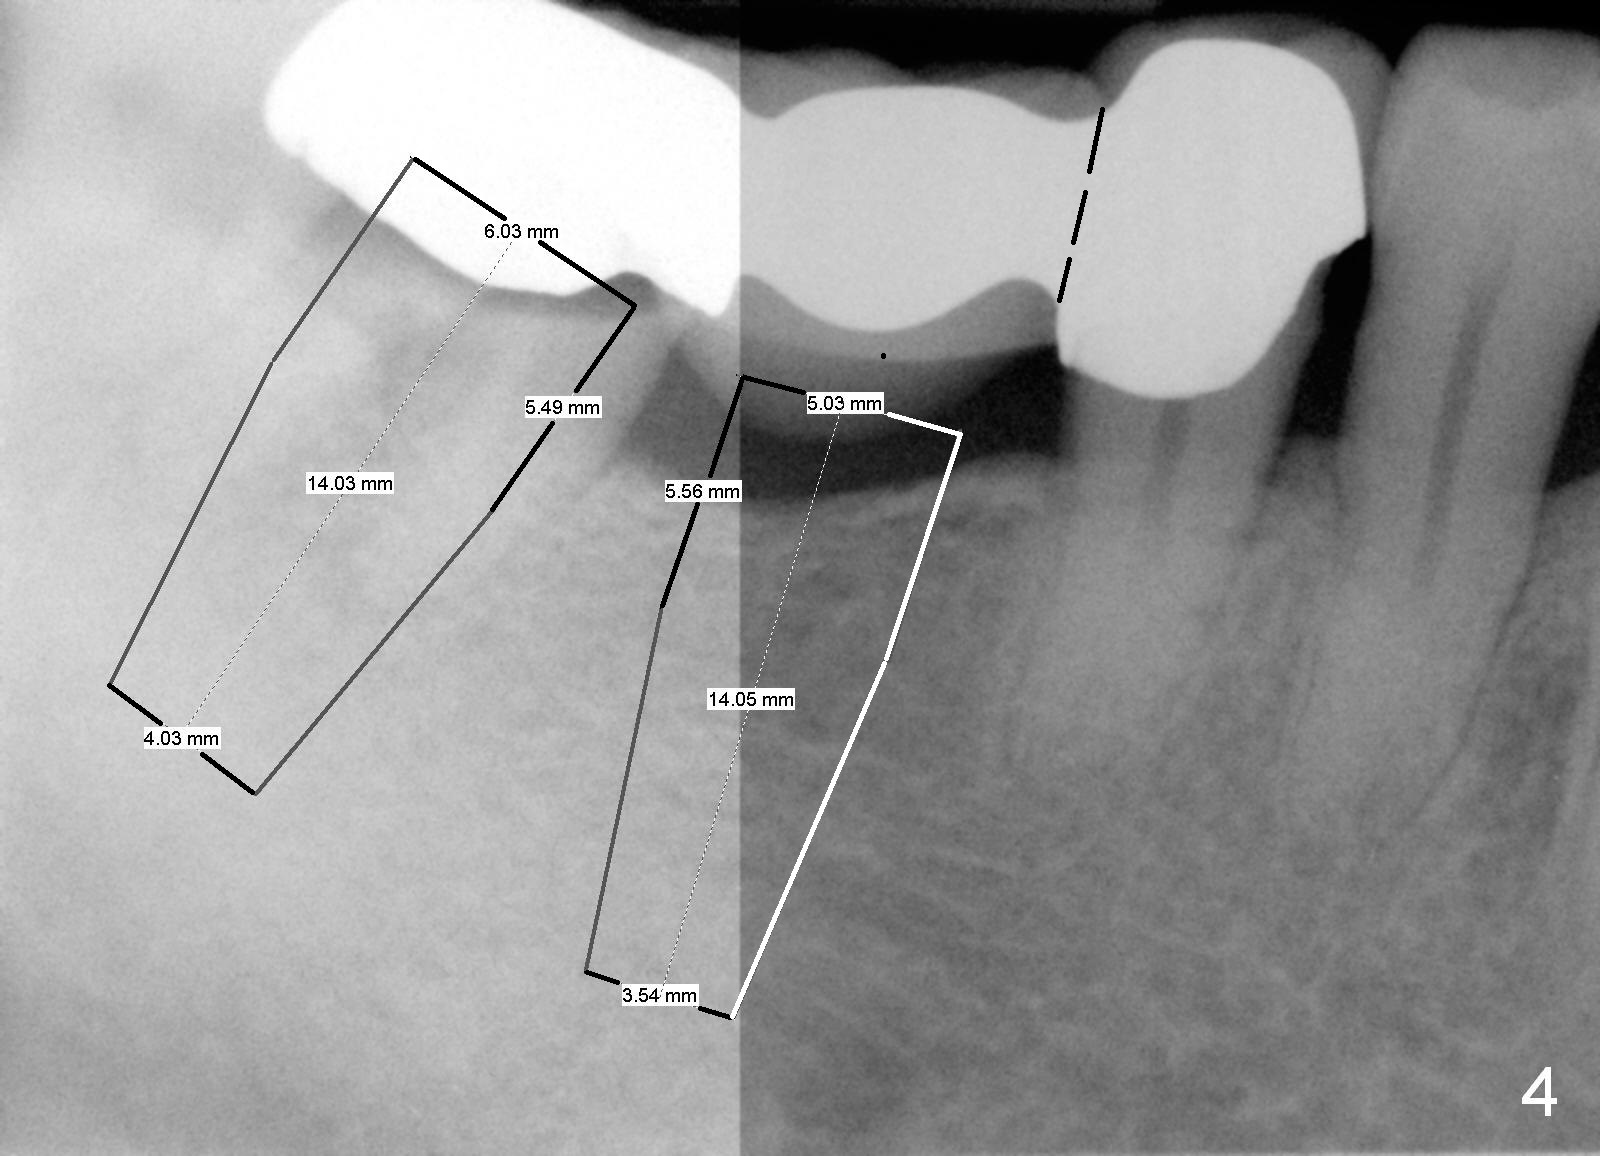

Before sectioning between #29 and 30 (Fig.4 dashed line), take Alginate impression for the lower right quadrant to fabricate a surgical stent.  Two implants are to be placed at the sites of #30 (5x14 mm) and 31 (6x14 mm) (Fig.3,4).